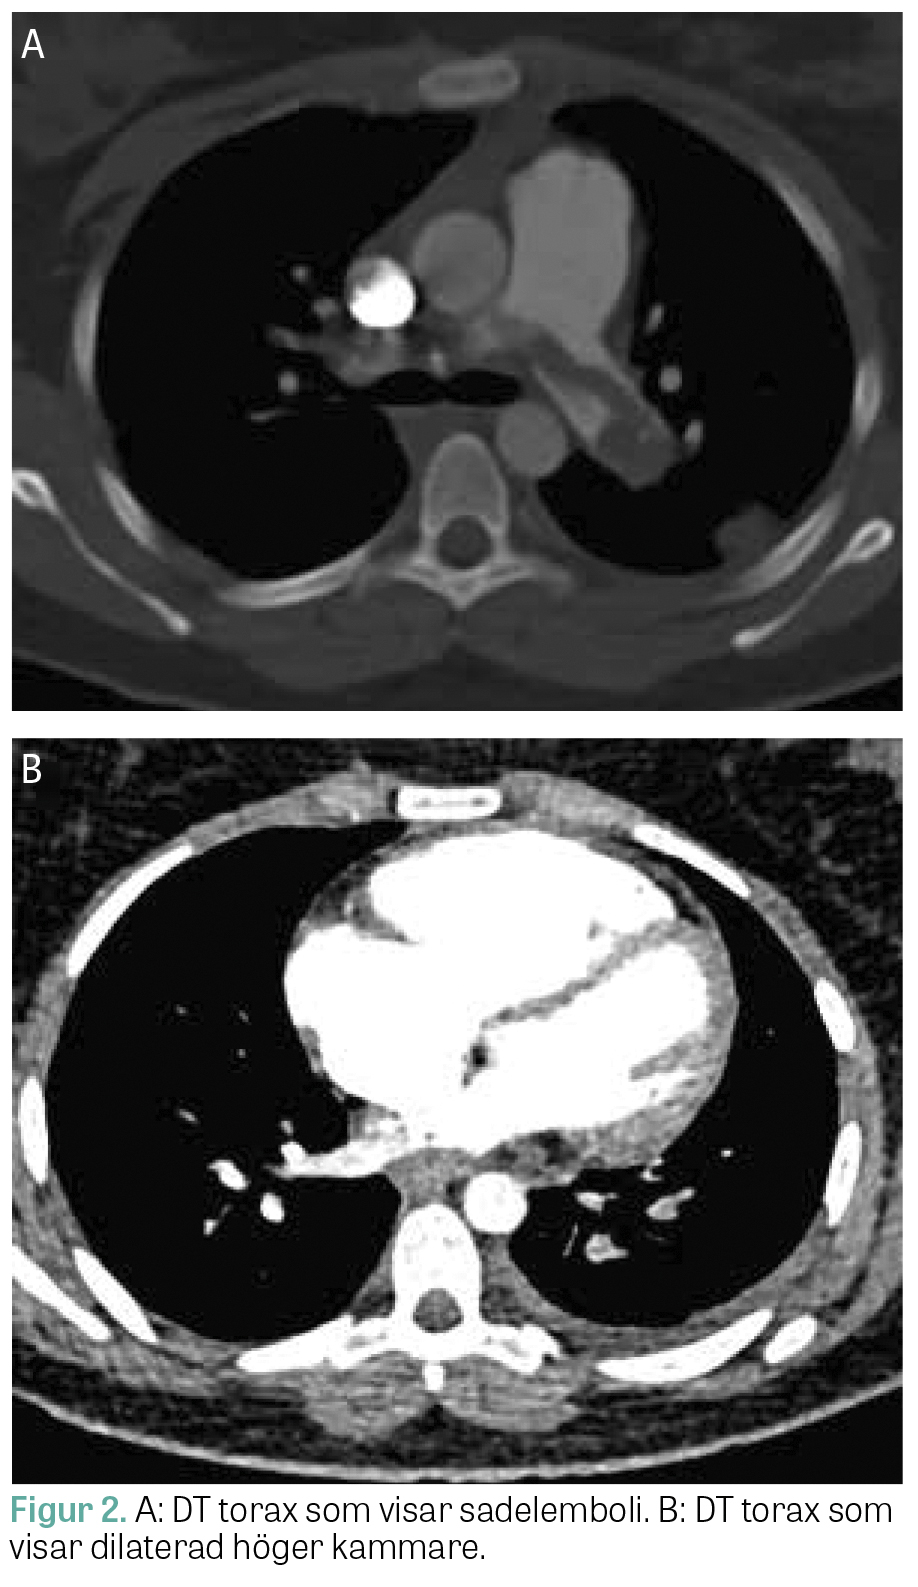

På akuten var patienten blek, takykard (130 slag/minut) och behövde 6 l syrgas för att hålla en saturation över 95 procent. Blodtrycket låg mellan 90 och 110 mm Hg systoliskt. EKG visade tecken på högerkammarbelastning, och datortomografi (DT) av lungartärer påvisade sadelemboli med bild som vid högerkammarpåverkan (Figur 2). Översiktligt ultraljud av hjärtat visade dilaterad högerkammare. Vid ankomst visade laboratorieprov förhöjt P-troponin T, 50 ng/l (referensvärde <15 ng/l), och P-NT-proBNP, 4 600 ng/l (<300 ng/l), samt förhöjt P-homocystein, 78 µmol/l (<15 µmol/l), medan S-kobalamin var 500 pmol/l (inom referens­intervall). Patienten lades in för trombolysberedskap och behandlades med lågmolekylärt heparin och cyano­kobalamin 2 mg × 2 per os. Patienten hade ingen tydlig fokalneurologi vid ankomst till akuten förutom upplevda parestesier i extremiteter samt yrsel, intermittent förvirring och desorientering. Vid närmare observation på avdelningen dag 2 noterades fortsatt förvirring, konfabulering och generell svaghet, som antogs vara sviter av lustgasbruket. Då det neurologiska tillståndet försämrades och talsvårigheter tillstötte gjordes dag 3 akut DT hjärna med venografi, vilken påvisade en färsk vänstersidig central infarkt. Parallellt genomfördes fullständig ekokardiografi som visade trombmassa i höger kammare samt shunt med höger–vänsterriktning på förmaksnivå. Trombolys bedömdes i detta läge vara kontraindicerad på grund av cerebral infarkt med blödningsrisk. Patienten behandlades i stället med heparinfusion och genomgick pulmonell endovaskulär trombektomi, vilken förlöpte komplikationsfritt.

Figur 2.